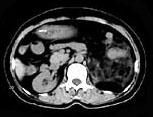

问题 女,64岁,左侧腰部胀痛,行CT扫描,下列说法正确的是 ( )

选项 A、考虑为左侧肾上腺来源的髓样脂肪瘤 B、考虑为腹膜后来源的脂肪肉瘤 C、该病灶密度不均匀,其内可见脂肪密度影,且呈不均匀强化 D、考虑为左肾来源的血管平滑肌脂肪瘤 E、左肾区可见一巨大的占位性病灶,境界较清楚,胰腺尾部受压向前推移

答案 CDE